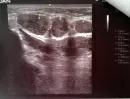

У меня на УЗИ под подбородком, сразу под нижней челюстью обнаружили 5 образований, самое большое образование 14×8. Образования гипоэхогенные округлые с четкими и ровными краями, однородные, аваскулярные, с дорсальным усилением. На очный прием челюстно-лицевого хирурга длинная очередь.

Что еще можно сделать в период ожидания? Стоит ли сделать КТ, чтобы получить больше информации об образованиях? Можно ли по КТ лучше понять, что это? Врач УЗИ засомневалась, что это кисты, опухоли или кисты?